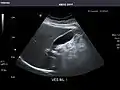

Left kidney

Kidneys: Right and left kidneys measure 11.5 cm and 12 cm in length respectively. No hydronephrosis. Small left lower pole kidney cyst.